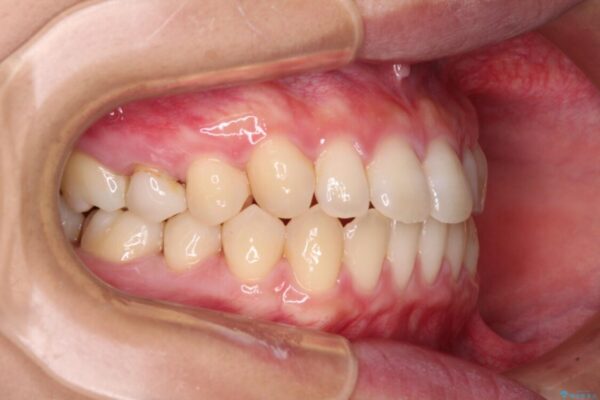

前歯の上下スペースと前歯の隙間を気にして来院された患者様です。

飲み込みや話をするときに舌を突出させる癖が強くあり、それが原因でスペースが空いていました。

舌癖を改善するためのトレーニングを行いながら、インビザラインにより上下の前歯の隙間を閉じていくこととしました。

治療前

• 隙間だらけの歯列 インビザラインで改善 治療前画像